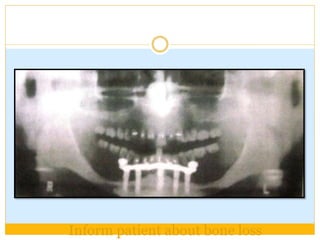

Inform patient about bone loss

DIVISION C(COMPROMISED BONE) Deficient in one or more dimensions  Resorption first occurs in width .The bone is called C-w  Then in height. The bone is called C-h  Posterior maxilla VS Anterior maxilla  Posterior mandible VS anterior mandible.

 Dimensions unfavorable in Width (c-w) :0 to 2.5mm  Height(c-h)-<12mm  Angulation (c-a)>30 degrees  CHS > 15mm